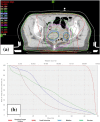

The incidence of endometrial serous carcinoma (ESC) has been increasing, and ESC is resistant to treatment. We report a patient with ESC who responded to radiotherapy for multiple recurrences. The first recurrence was detected in the vaginal wall and left internal iliac lymph node 5 months after the initial treatment. Concurrent chemoradiotherapy (CCRT) was administered. Radiation was delivered using the intensity modulated radiation therapy technique. The second recurrent tumor was detected in the right internal iliac lymph node after 4 months, and CCRT was conducted. After 4 months, the third recurrence was detected in the right common iliac node, and CCRT was performed. After 8 months, the fourth recurrence was detected in the horizontal portion of the duodenum, and radiotherapy was administered. After 9 months, the fifth recurrence was detected in the vaginal wall. Interstitial brachytherapy was conducted. Grade 2 gastrointestinal injury, nausea and radiodermatitis were observed. During the subsequent 13-month follow-up, there has been no recurrence. Although ESC is resistant to treatment, radiotherapy could be effective in some cases. Even when multiple recurrences occur, radiotherapy may be considered a treatment option if the irradiation level is permissible.